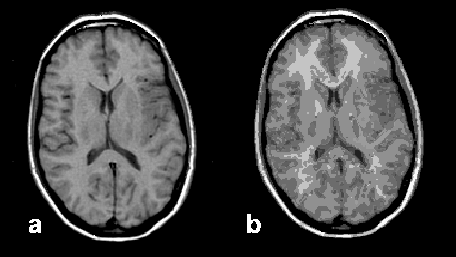

Figure 15-11:

Image segmentation: (a) original brain image, and (b) segmented image presenting 90 different tissue com­­po­nents.